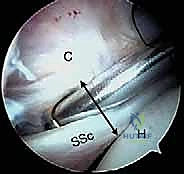

2. إحداث الثقوب (Portals) واستكشاف المفصل

يقوم الدكتور هطيف بعمل 3 إلى 4 ثقوب صغيرة جداً حول الكتف. يُدخل كاميرا المنظار (Arthroscope) لعمل جولة استكشافية شاملة لداخل المفصل، وتقييم الغضاريف، أوتار الكفة المد